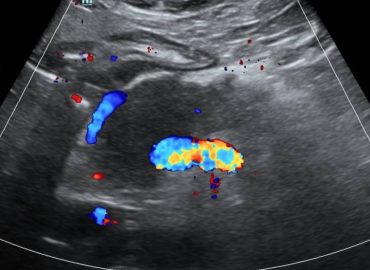

Sexo: masculino Edad: 26 años MC: dolor en región lumbar izquierda